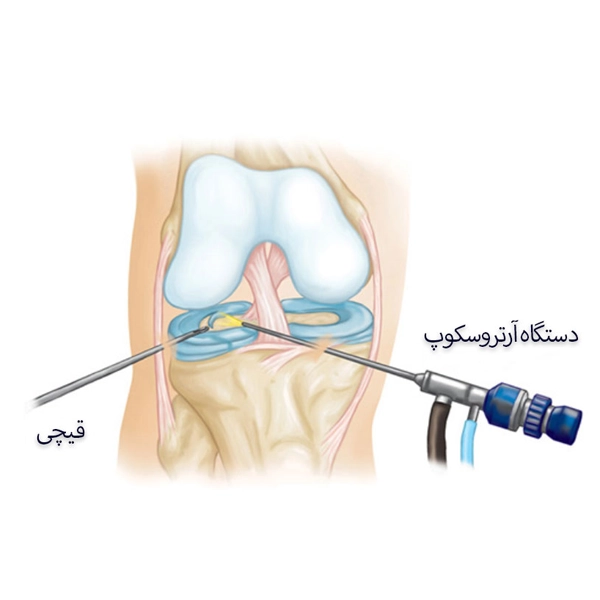

عمل مینیسک زانو عموماً به روش آرتروسکوپی انجام میشود که یکی از کمتهاجمیترین تکنیکهای جراحی ارتوپدی به شمار میرود. در این روش، جراح از طریق برشهای بسیار کوچک در اطراف زانو، دوربین کوچکی به نام آرتروسکوپ و ابزارهای جراحی مخصوص را وارد مفصل میکند. این تکنیک باعث کاهش درد پس از عمل، کوتاه شدن دوران نقاهت و به حداقل رساندن خطر عفونت میشود.